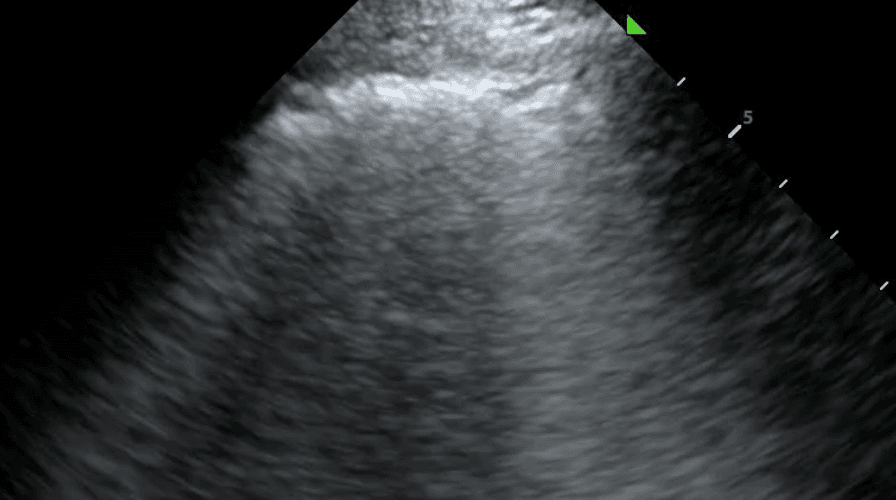

Lung ultrasound can be a valuable tool in the diagnosis and management of TB patients, particularly in settings where other imaging modalities such as chest X-ray or computed tomography (CT) scan may not be readily available or feasible. While lung ultrasound findings in TB can vary depending on the stage and extent of the disease, some distinct features may be picked up.

Lung ultrasound will also demonstrate diseased lungs that are filled with fluid or cellular debris. Lung consolidations often have bright air bronchograms, which represent air trapped in fluid filled bronchi.